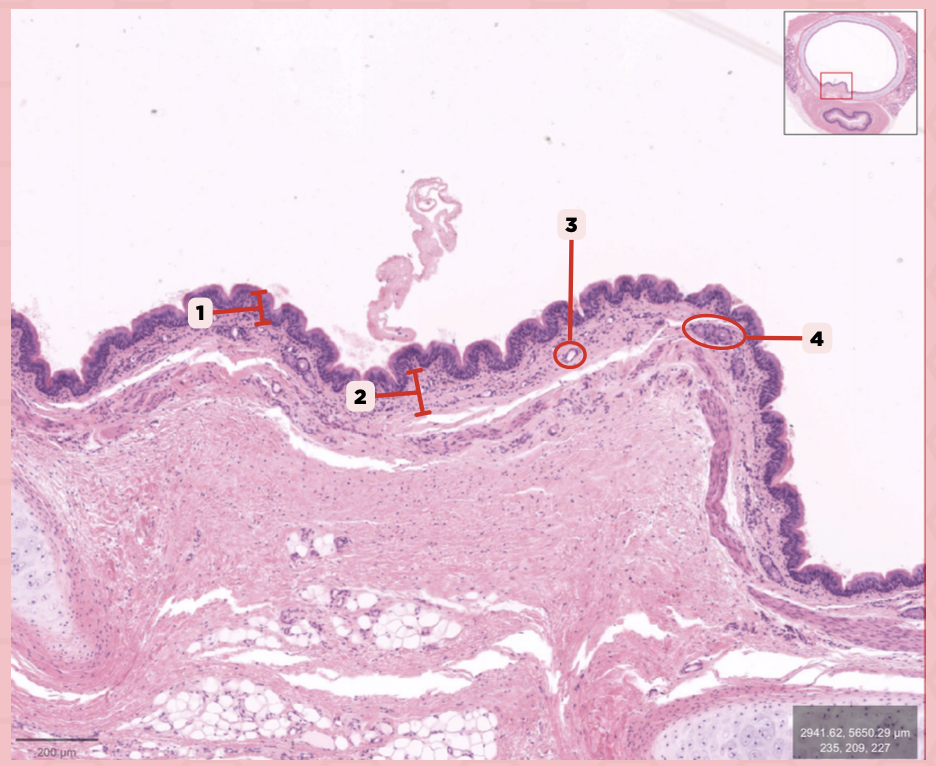

Identify the structure labeled as 1.

Nasal septum

Identify the structure labeled as 2.

Nasal cavity

Identify the structure labeled as 3.

Hard palate

Identify the structure labeled as 4.

Mucosal Associated Lymphoid Tissue (MALT)